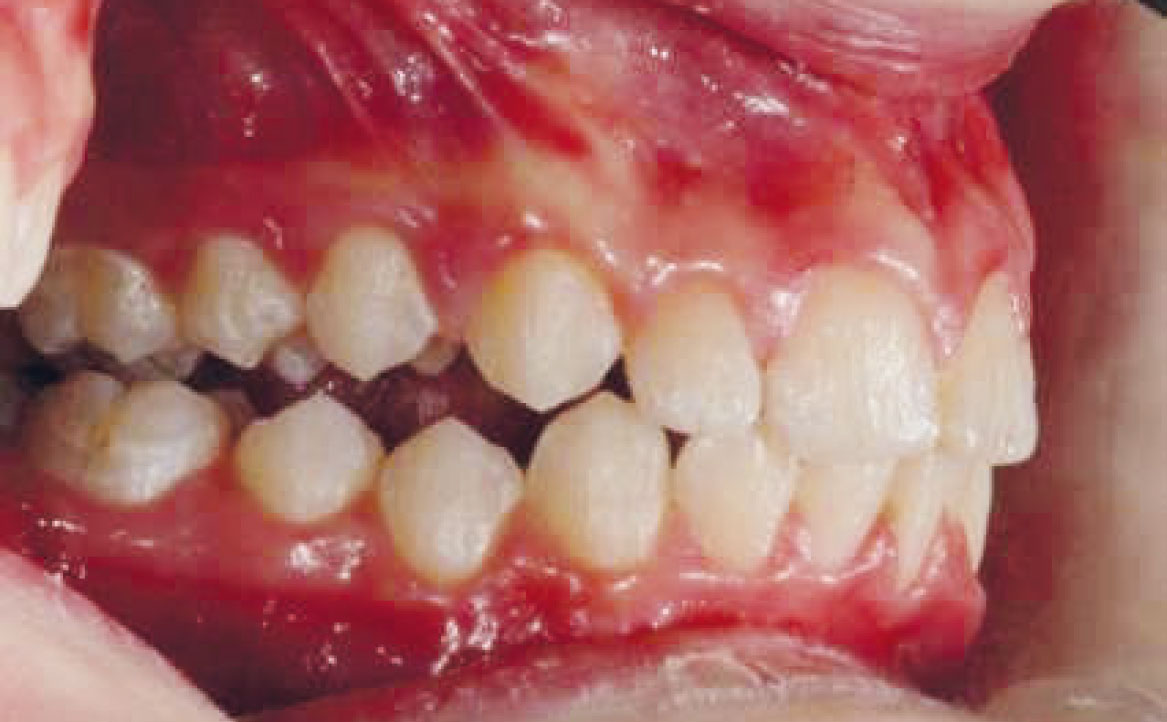

Paziente di genere femminile di otto anni affetta da una malocclusione di classe II sia dentale che scheletrica, associata a una condizione di retrusione mandibolare e contrazione dell’arcata superiore. Non si rilevano problemi dentali significativi.

Viene eseguita la consueta raccolta dei records: fotografie intra ed extra orali, modelli e indagini radiografiche di primo livello (OPT e teleradiografia latero-laterale) (fig. 2-11).

La buona collaborazione della paziente ha consentito di ottenere un buon avanzamento mandibolare, la correzione delle classi canina e molare (ben evidenti nelle fotografie intra orali mostrate in fig. 15 e 17). Il morso aperto residuo verrà corretto mediante immediato inizio della terapia ortodontica fissa al fine di abbreviare la durata complessiva del trattamento.